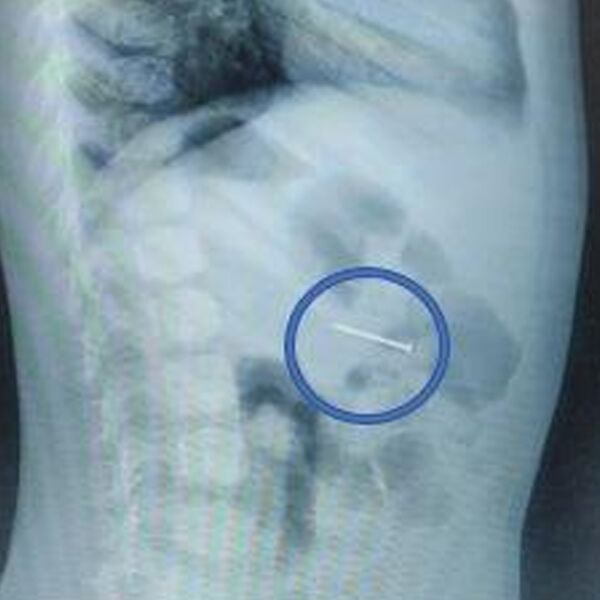

Врачи Детского клинического центра имени Л.М. Рошаля спасли четырехлетнего мальчика, который проглотил гвоздь. Об этом сообщили в пресс-службе минздрава Московской области.

При поступлении ребенка в больницу его мать рассказала, что сын проглотил гвоздь, который нашел дома: женщина пояснила, что у них в квартире идет ремонт. Сам момент проглатывания инородного предмета она не видела, но после ребенок начал кашлять, а в слюне появились следы крови.

Обследование подтвердило версию родительницы.

«Своевременно начатое вмешательство помогло избежать серьезных последствий. Сперва мы сделали рентгенографию – она подтвердила наличие гвоздя в желудке, а после выполнили гастроскопию: с помощью эндоскопических щипцов аккуратно захватили гвоздь за острый конец и извлекли его через ротовую полость», — поделился врач-эндоскопист Руслан Мусаев, добавив, что манипуляция заняла около 20 минут.

После этого мальчик еще несколько часов находился под наблюдением врачей. В тот же день его выписали домой.